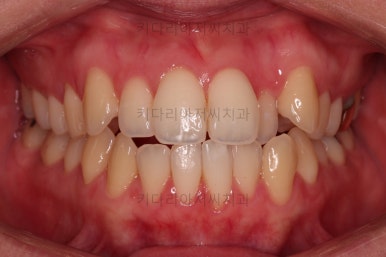

1년 2개월이라는 비교적 짧은 기간안에 원하시는 부분을 깔끔하게 개선했습니다.

전후 비교해 볼게요.

이번 환자분도 삐뚤한 치열을 비발치로,심지어 미니스크류 사용도 없었고 치간삭제도 거의 하지 않았는데요.

입이 나오거나 뻐뜨러지는 느낌 전혀 없죠?

진료 메카니즘을 잘 구성하고 철사를 잘 다뤄주면 좋은 결과를 얻을 수 있답니다.

이상 비발치로 덧니를 개선한 치료사례였습니다.